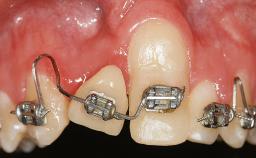

A 30-year-old woman was referred by her general dentist for evaluation of an esthetic complication related to previous implant treatment for congenitally missing maxillary lateral incisors. The patient’s chief complaint was the inadequate esthetic appearance of her smile. The case demonstrates the use of a combined approach to achieve optimal results. Two different flap designs - a tunnel technique and a coronally advanced flap - are employed based on the surgical objectives for the affected site.